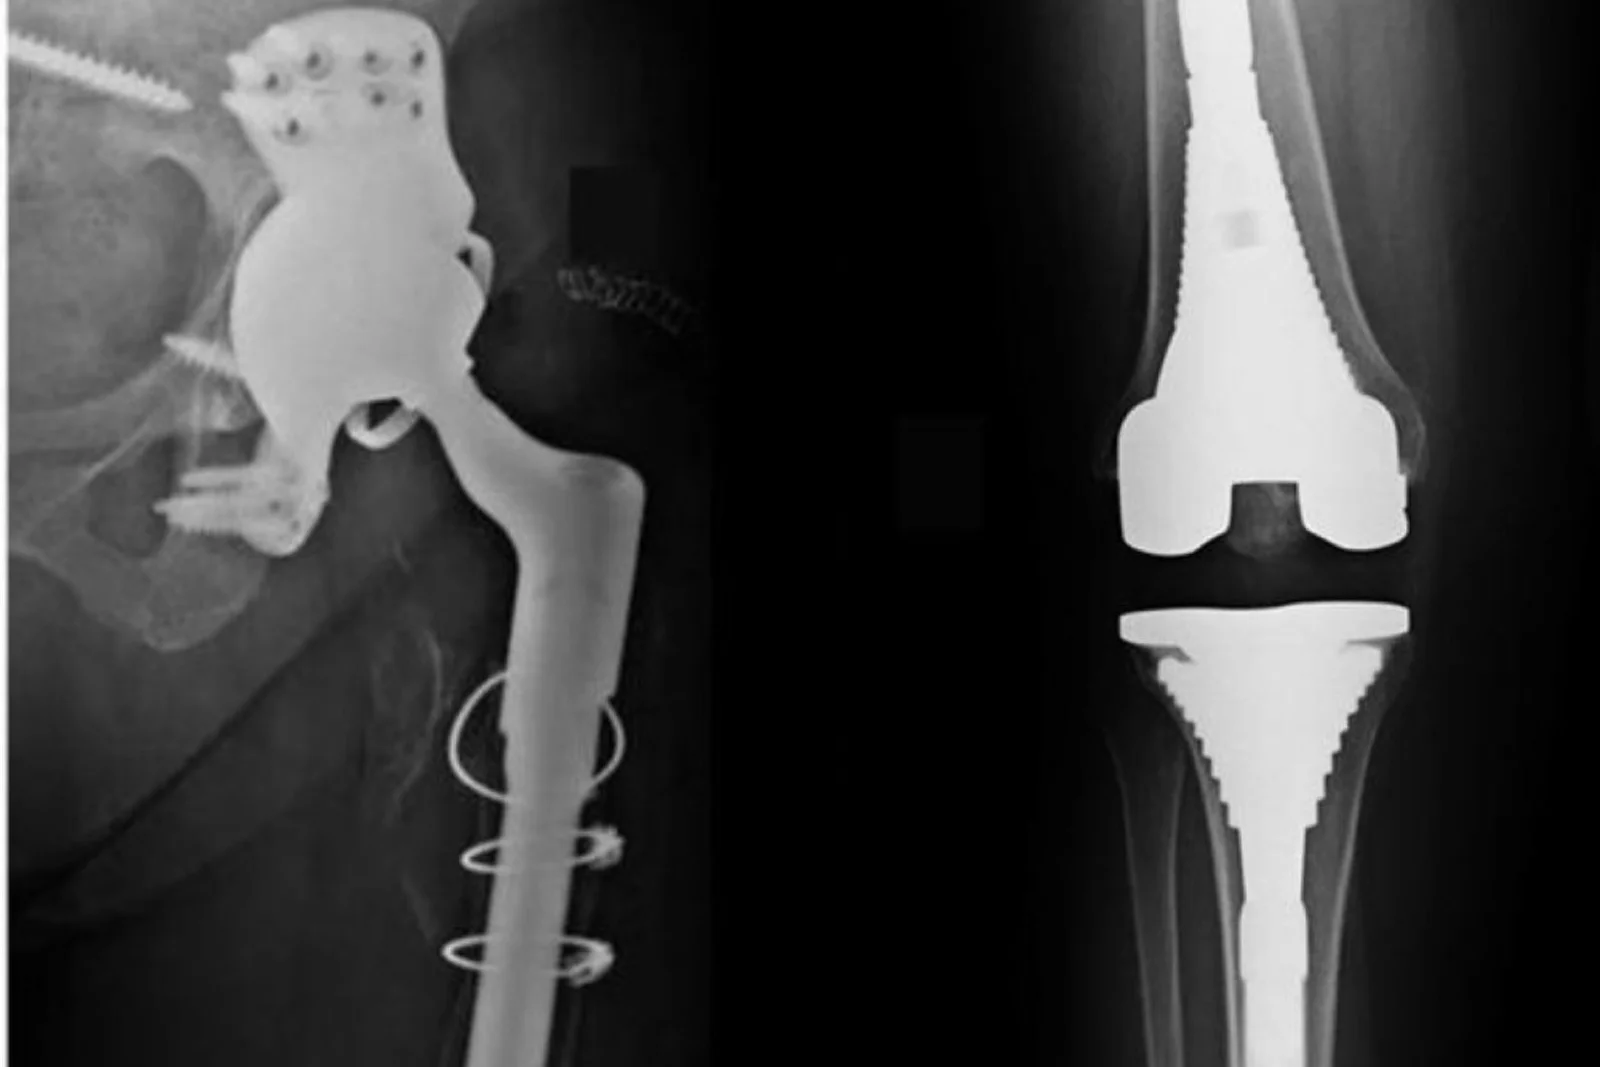

Total hip replacement surgery for degenerative hip disease, arthritis or trauma.

Total knee replacement for arthritis or deformity.

Complex revision surgeries for failed implants or infection.